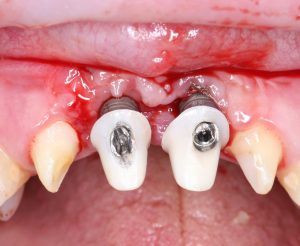

Реставрация фронтальной группы зубов.

Имплантация — Станислав Васильев       Протезирование — Давид Ахинян

Прежде, чем приступить к аугментации (пластике) лунок зубов, мы подготовили лунки для имплантатов. В таких клинических случаях нет необходимости в использовании шаблона. Вместо этого, мы применяем общепринятые правила позиционирования и соблюдаем рекомендации производителя по хирургическому протоколу:

В процессе ирригации лунки промываются, что позволило нам еще раз подтвердить ранее сделанные выводы. С помощью аналогов имплантатов, входящих в хирургический набор Xive, мы проверили возможность стабилизации имплантатов в будущих лунках. Исходя из правил подбора и позиционирования имплантатов (я очень рекомендую почитать об этом здесь>>) мы остановились на Xive S диаметром 3,4 мм и длиной 13 мм.

Установка имплантатов

По ряду уже упомянутых выше причин, для решения этой клинической задачи мы выбрали имплантаты Xive. Лунки для них мы уже приготовили. возможную первичную стабильность оценили. Имплантаты мы установили с усилием чуть больше 15-20 Нсм — такого крутящего момента более, чем достаточно, особенно если учесть, что временные коронки будут соединяться между собой.

Подробно о том, что такое крутящий момент и хирургический протокол можно прочитать здесь>> и тут>>, соответственно. Из-за использования специальных индивидуализируемых временных абатментов, имеющих только три положения, нам нужно позиционировать платформу имплантатов по граням. Это очень просто  — мы выводим вырез абатмента TempBase (он входит в комплект поставки) вестибулярно.